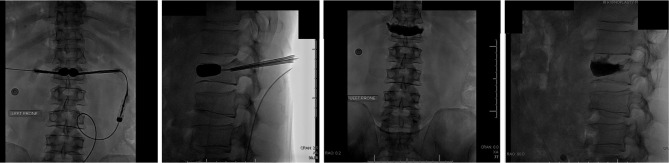

Case description: We present a clinical case of a 59-year-old diabetic male patient with a recent foot ulcer, positive for Corynebacterium striatum and Enterococcus. Shortly after discharge, the patient was admitted for signs of septicemia positive for Corynebacterium striatum and Pseudomonas aeruginosa. The patient had also sustained an acute L1 compression fracture at the time of septic presentation. A KP was performed, just 10 days after original septicemia diagnosis. 5 months later, the patient presented with continued incapacitating back pain at the operative site, and a diagnose revealing osteomyelitis at the location of the L1 KP positive for Corynebacterium striatum, treated with vancomycin and daptomycin. The cement and surrounding bone were compromised and instability developed, requiring an L1 vertebrectomy with T9-L4 posterior fusion with allograft. The patient has been followed for 1.5 years postoperatively with full recovery, decreased pain, and improved quality of life. We discuss the importance of KP safety in the setting of recurrent systemic infection.

Abstract Image